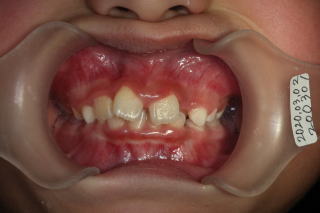

2020年03月02日 初診

上顎前歯叢生反対咬合